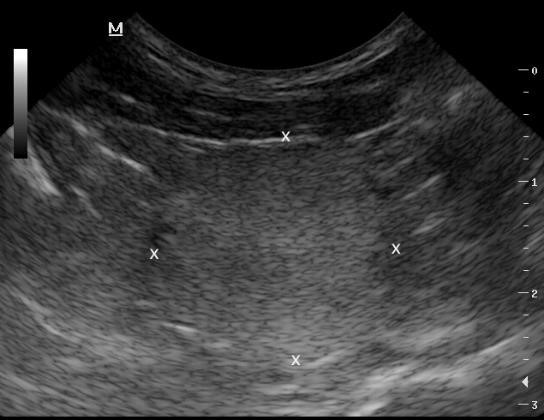

How does the overall echogenicity compare to the normal prostate?

What is the liekly differential?

Heterogenous

More echogenic

Bigger too

Diagnosis:

BPH

Cant rule out infection = not many cysts